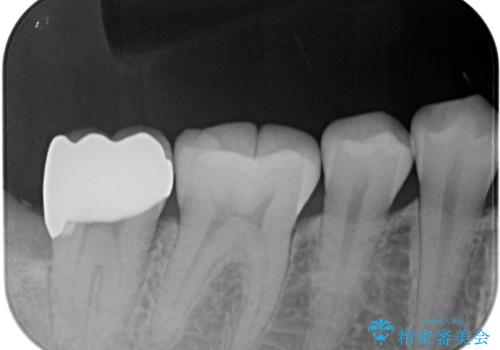

親知らず抜歯の症状が治まってから手前の歯の状態を確認しましたが、特に症状は認められませんでした。

それでも生活歯髄療法になる可能性を考慮して、ラバーダム装着下にてむし歯を除去し、神経組織が露出寸前であったためMTAセメントによる歯随保護を行いました。

処置後神経の反応が正常であることを確認して、オールセラミッククラウンを装着しました。